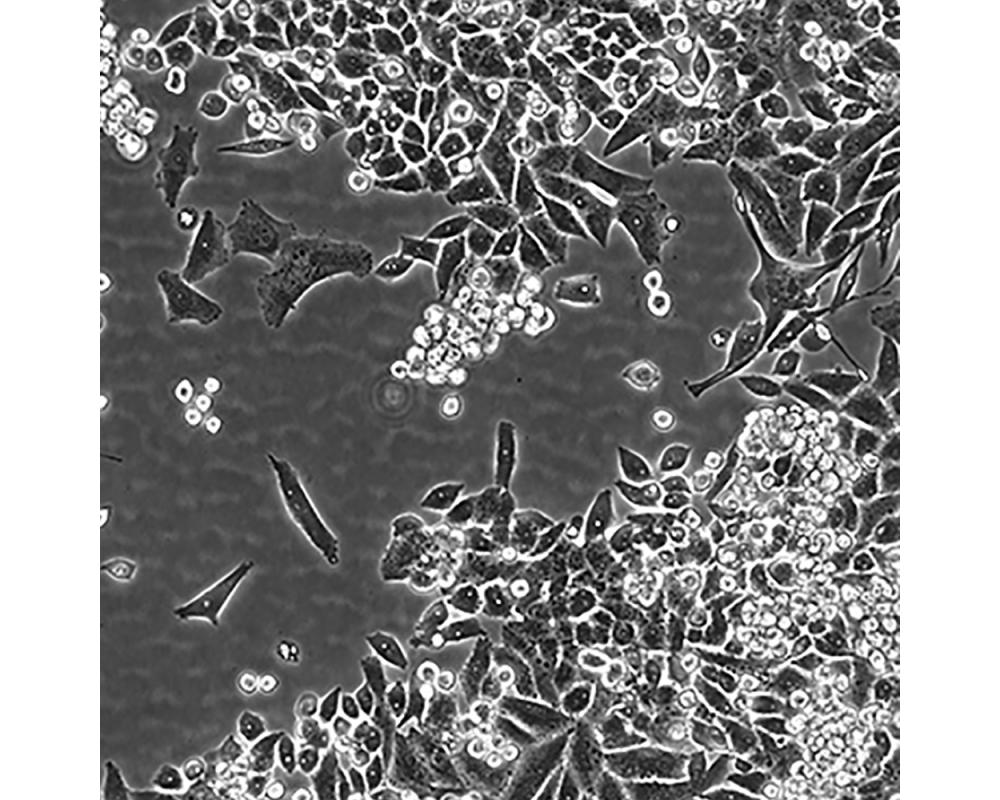

MiaPaCa-2

中文名稱 人胰腺癌細胞

組織來源 胰腺導管癌;男性

生長特性 貼壁

培養基 1640,90%;FBS,10%;雙抗。

培養條件 Atmosphere: Air, 95%; CO2, 5%。Temperature: 37℃

細胞傳代步驟 如果細胞密度達80%-90%,即可進行傳代培養。1. 棄去培養上清,用不含鈣、鎂離子的PBS潤洗細胞1-2次。2. 加2ml消化液(0.25%Trypsin-0.53mM EDTA)于培養瓶中,置于37℃培養箱中消化1-2分鐘,然后在顯微鏡下觀察細胞消化情況,若細胞大部分變圓并脫落,迅速拿回操作臺,輕敲幾下培養瓶后加少量培養基終止消化。3. 按6-8ml/瓶補加培養基,輕輕打勻后吸出,在1000RPM條件下離心4分鐘,棄去上清液,補加1-2mL培養液后吹勻。4. 將細胞懸液按1:2到1:5的比例分到新的含8ml培養基的新皿中或者瓶中。